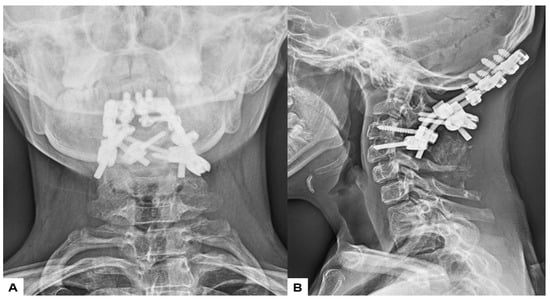

2.5. Postoperative Imaging